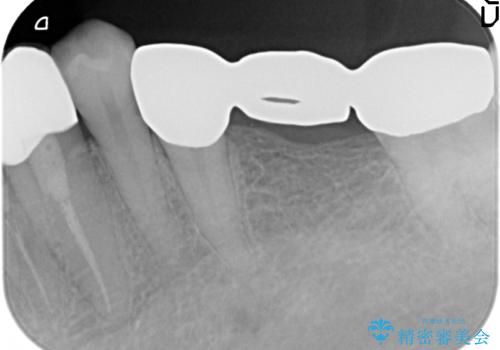

- 左下の銀歯を前の歯に合わせて白くしたいといらっしゃった方の症例です。

前歯部のシェードに合わせ、左下4及び左下567ブリッジをオールセラミッククラウンにて補綴しました。

今回用いたオールセラミッククラウンはジルコニアフレームという白い素材の上にセラミックを盛っているため、審美性が非常に高いのが特徴です。

また、ジルコニアは人工ダイヤモンドの材料にも使われているほど高い強度を持っており、そのためオールセラミッククラウンは審美性だけでなく、奥歯やブリッジの補綴も可能とするクラウンです。